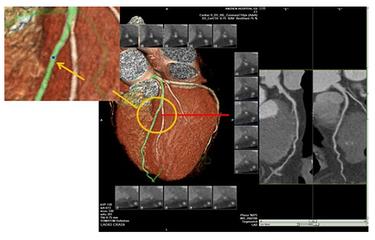

La naissance de la tomodensitométrie à 64 rangs et le développement de la technologie de suivi dynamique nous ont permis d'examiner les vaisseaux cardiaques de manière non invasive afin d'identifier la présence et l'étendue de la sténose dans les vaisseaux coronaires. Cette technique a bénéficié à de nombreux patients souffrant d'oppression et de douleurs thoraciques et ayant peur des aiguilles et du bloc opératoire. Le principe de cet examen est le suivant : un agent de contraste est injecté par voie intraveineuse et un balayage en spirale des vaisseaux coronaires remplis de produit de contraste est effectué par tomodensitométrie. Chaque tranche de balayage de l'artère coronaire est ensuite combinée pour former une image de l'artère coronaire grâce à la technologie de combinaison d'images.

Ce test est non invasif et sûr, mais il présente un certain nombre de lacunes, ① le contrôle du rythme 64 rangs CT exige que la fréquence cardiaque soit contrôlée à 60 battements / min ou moins, plus rapide 128 rangs et CT à double source exige également que la fréquence cardiaque soit contrôlée autant que possible dans les 70 battements / min ou moins ; ② Coronary CT entre le cœur de l'examen ordinaire et l'angiographie des artères coronaires, mais aussi et l'angiographie des artères coronaires, comme les dommages de rayonnement et de contraste, si les symptômes sont très clairs. Si les symptômes sont très clairs, il est préférable d'effectuer le test d'imagerie en plus de l'examen, qui peut également être traité directement ; ③ souvenez-vous de cette phrase, si le scanner coronaire indique que vous n'avez pas de maladie coronarienne, la crédibilité de cette phrase peut atteindre 99 %, mais si le scanner coronaire indique que vous avez une maladie coronarienne, la crédibilité de cette phrase n'est que de 70 %.

5. angiographie coronaire par tomodensitométrie (CT coronary angiography)La procédure consiste à injecter un agent de contraste iodé dans un vaisseau sanguin. Elle consiste à injecter un agent de contraste iodé dans un vaisseau sanguin et à utiliser la tomodensitométrie (CT) pour examiner les artères coronaires afin de vérifier la présence de malformations, de ponts dans le myocarde, de plaques et de sténoses dans les artères coronaires. L'avantage de cette méthode est qu'elle est "non invasive" et qu'il n'est pas nécessaire d'introduire un cathéter dans les artères coronaires. Cependant, comme il s'agit d'une radiographie, il est préférable d'examiner les calcifications, mais il y a des limites à l'examen des sténoses, qui n'est pas très précis (cela dépend de l'instrument et du niveau de compétence de l'examinateur), et en outre, un rythme cardiaque rapide ou irrégulier affectera également l'effet de l'imagerie. Par conséquent, cette méthode est la meilleure pour exclure une maladie coronarienne et moins précise pour diagnostiquer une sténose. En outre, au cours de l'examen, 80 à 100 ml d'agent de contraste iodé sont injectés par voie intraveineuse. Premièrement, il existe un risque d'allergie (le test cutané peut ne pas être détecté), deuxièmement, l'agent de contraste doit être excrété par les reins, ce qui est dommageable pour les reins, et un petit nombre de patients peut développer une "néphropathie de contraste" (néphropathie de contraste), avec une déficience ou une insuffisance rénale, de sorte qu'un traitement d'"hydratation" est nécessaire avant et après l'examen. Il est donc nécessaire de s'hydrater avant et après l'examen.

- 冠Le CTA de Pulse est un plombier débutantL'angiographie coronarienne est en fait une sorte d'examen tomodensitométrique. Lors de cet examen, un médicament est injecté dans la veine de la main, ce médicament est l'agent de contraste. Lorsque l'agent de contraste atteint l'artère coronaire, il montre l'ombre de cette artère coronaire et permet de déterminer s'il y a un blocage ou un rétrécissement de l'artère coronaire.Les troncs principaux des artères coronaires et certaines des plus grosses branches sont plus clairement visibles, tandis que les plus petites branches sont moins bien représentées.

ATC coronaire

L'angiographie coronarienne par tomodensitométrie est un moyen d'examiner les artères coronaires en combinaison avec l'angiographie, ce qui permet de diagnostiquer la maladie coronarienne et d'examiner et de juger l'emplacement des plaques coronaires, en particulier l'étendue des plaques calcifiées. L'angiographie coronarienne par tomodensitométrie permet également d'évaluer si le flux sanguin est régulier au niveau du site du stent chez les patients atteints de maladie coronarienne et auxquels on a implanté des stents. En outre, pour les patients souffrant de douleurs thoraciques, l'angiographie coronarienne par tomodensitométrie permet de détecter des problèmes tels que l'aortique, le pneumothorax et le pneumothorax. Pour les patients souffrant de douleurs thoraciques, l'angiographie coronaire peut être utilisée pour dépister les problèmes aortiques, pulmonaires et de pneumothorax, mais elle n'est pas recommandée pour les patients présentant une forte suspicion d'infarctus aigu.

Cependant, pour une partie de la population qui ne présente pas de risque élevé de maladie coronarienne, les médecins recommandent parfois un dépistage de la sténose des artères coronaires à l'aide de la technologie CTA coronaire.Bien que la précision de l'angiographie coronaire soit encore loin de celle de la coronarographie, elle permet d'exclure les patients dont la coronaropathie est négative.